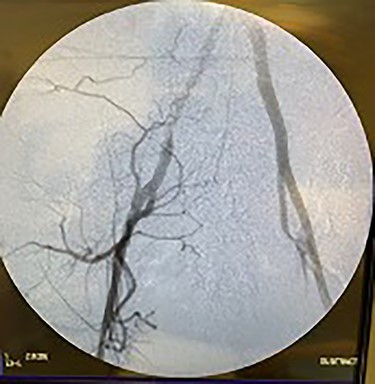

Catheter arteriogram results showed significant occlusion of the left iliac artery (Figs 3 and 4), the right iliac artery (Fig. 1), as well as the distal abdominal aorta (Fig. 2). There were numerous collateral vessels noted, indicating the presence of long-standing proximal stenosis (Fig. 1). The decision was made to use angioplasty to help widen the areas of stenosis. An 8 mm × 40 mm Passeo balloon was advanced from the right femoral artery into the left iliac artery (Fig. 7) and insufflated to 6 mmHg (Fig. 6). The balloon was allowed to remain expanded for 1 min and then was deflated. Next, the distal aorta was repaired in a similar fashion. The balloon was advanced into the distal aorta from the right femoral access and insufflated to 12 mmHg (Fig. 8). The balloon was allowed to remain expanded for 90 s.

Fluoroscopy of right iliac artery showing vast collateral vascular formation, indicating long-standing proximal obstruction.